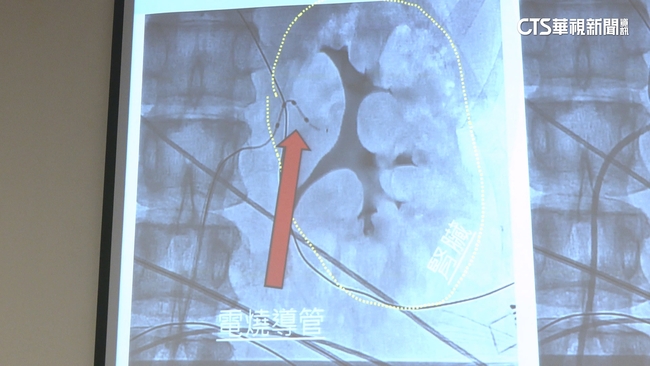

醫生說交感神經阻斷術有分,傳統手術沒全身麻醉,只打鎮定劑,手術很快1小時就能完成,但不保證能成功將神經阻斷;新手術要全身麻醉,加上使用最新的3D神經定位技術,刺激電擊神經時,可以找到是哪條神經有狀況,能精準電燒,時間比較長要3到4小時。

中國醫藥大學附設醫院心臟電生理科醫師鍾偉信說:「藉由3D定位的系統,去把神經找出來,在找到神經的地方的時候,去刺激它,血壓就明顯的上升。」醫生表示,傳統的手術就是沒有精準定位,神經肉眼又看不到失敗率高,新手術有3D定位能在手術中精準阻斷神經,成功率高,而這也是6位數的自費項目,讓有需要的患者多一種選擇。